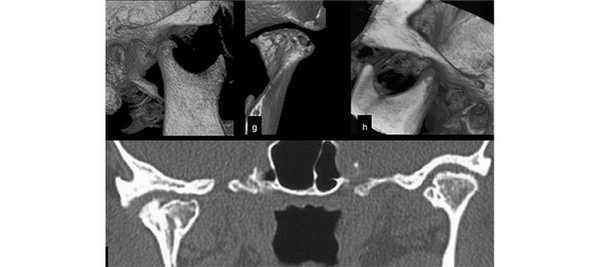

Более ранние изменения обнаруживали только на компъютерных томограммах: сужение рентгеновской суставной щели, появление эрозии в кортикальном слое суставной поверхности головки и суставного бугорка, субхондральный склероз кости.

Наиболее характерным рентгенологическим симптомом в этой клинической группе была асимметрия линейных размеров головок нижней челюсти у 27 (51,0±6,9 %) больных с сохранением их нормальной структуры. Результаты КТ ВНЧС, проведенных у 18 (13,7±3,0 %) пациентов с артрозом и 12 (40,0±9,0 %) пациентов с деформирующим артрозом, в целом повторяют характерные рентгенологические симптомы, полученные при проведении рентгенографии ВНЧС (по Парма) и ортопантомографии, при этом указанные изменения ВНЧС встречались в 2—3 раза чаще, чем на рентгенограммах ВНЧС. Кроме того, КТ позволяла обнаружить более тонкие структурные изменения костной ткани суставов, которые не диагностировались на рентгенограммах.

На КТ пациентов с артрозом ВНЧС намного чаще определялись изменения структуры головок нижней челюсти: деформация — у 17 (13,0±3,0 %) пациентов, костные разрастания — у 15 (11,5±2,8 %) лиц, остеопороз — в 9 (6,9±2,2 %) случаях. Утолщение замыкательных пластинок суставной ямки и бугорка на КТ встречалось у 12 (9,2±2,4 %) пациентов.

КТ ВНЧС позволила в 2—3 раза чаще выявлять рентгенологические симптомы, которые не определялись на рентгенограммах и ортопантомограммах. Чаще такие изменения касались тонкой структуры костной ткани головки нижней челюсти, суставной ямки и бугорка.